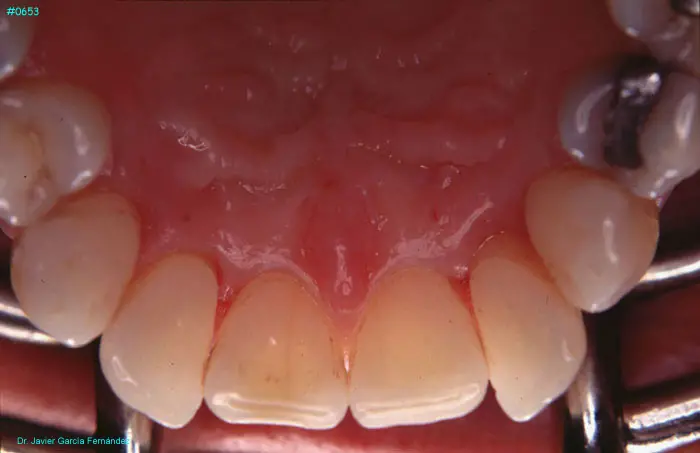

Atlas of Surgical Techniques in Periodontics. Chapter III. Atlas de Técnicas Quirúrgicas en Periodoncia